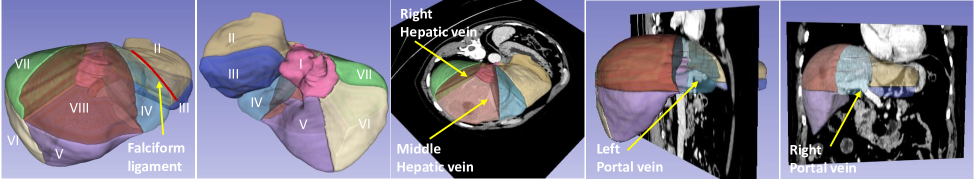

Effective treatment for primary liver cancer relies on two main procedures: liver resection and radiofrequency ablation [12]. Both approaches depend on accurate Couinaud segmentation, to reduce the risk of main vessel puncture, and to guide the placement of ablation needles [1, 13]. Couinaud segmentation divides the liver into eight functionally independent segments. The right-, middle- and left-hepatic veins divide the liver into four sections. These sections are then further split by the horizontal plane defined by the portal vein, as shown in Fig. 1.